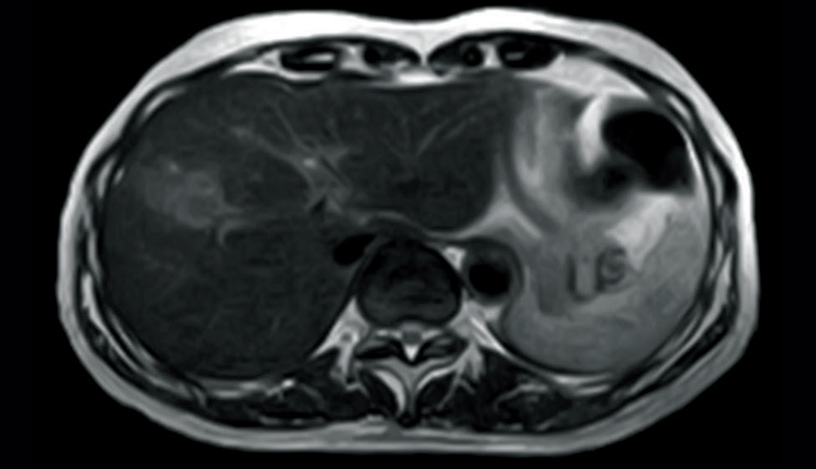

T2WI